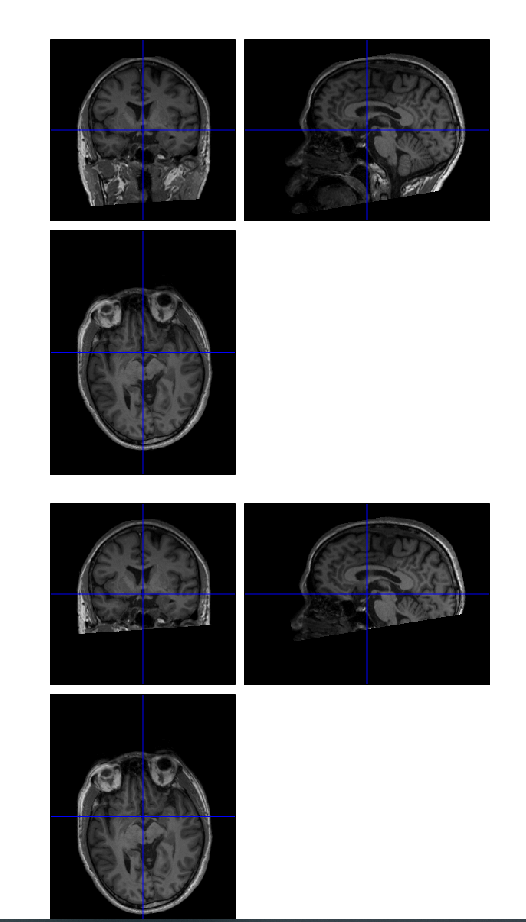

Dear Chris Rorden, when I use dcm2nii to convert DICOM

images to NIfTI, the output files have three kinds, original nii,

o.nii, co.nii. Many people recommend to use co.nii for vbm segment

and normalization, but I found some co.nii seemed abnormal, some

brain tissue seemed being cropped. Can such co.nii be used for vbm

analysis, can you give me some suggestions. Thank you very much

The cropping assumes that you are using a T1 scan that was

approximately oriented in the AC-PC plane (anterior commissure,

posterior commissure) which is typical for MRI. It looks like your

scans are with the angle of rotation more similar to CT scans

(where one wants to reduce radiation to the eyes and minimize

artifacts from dental fillings). In this case, the dcm2niix

cropping function will not work well. I would be especially careful

normalizing you r scans to standard space, as the slice angle does

not match the template so there may be a poor starting estimate.You